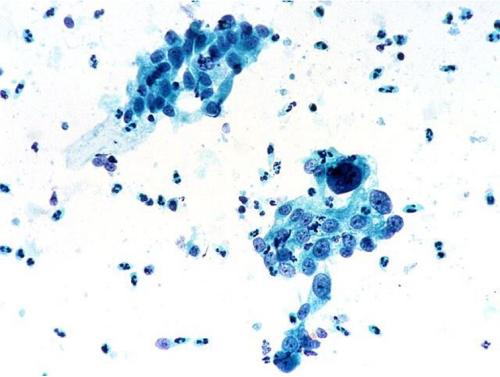

病毒往往會(huì)依賴宿主細(xì)胞進(jìn)行復(fù)制,但病毒是如何誘導(dǎo)宿主轉(zhuǎn)錄自身的遺傳信息來制造病毒顆粒的呢?幾十年來,科學(xué)家們一直在研究一種名為λ(lambda)的噬菌體來試圖找到答案。

近日,一項(xiàng)刊登在國際雜志Molecular Cell上的研究報(bào)告中,來自柏林夏里特醫(yī)學(xué)院的科學(xué)家們利用高分辨率的冷凍電鏡技術(shù)成功解析了上述過程。

沒有宿主就沒有病毒,盡管病毒能通過宿主外環(huán)境來傳播擴(kuò)散,但其仍需要宿主來進(jìn)行繁殖,病毒缺少復(fù)雜的結(jié)構(gòu)來將遺傳信息進(jìn)行轉(zhuǎn)錄并轉(zhuǎn)化成為新的病毒顆粒,這也就是為何所有病毒都需要使用宿主細(xì)胞的分子結(jié)構(gòu)的原因;長期以來,科學(xué)家們一直在研究病毒成功利用宿主細(xì)胞功能的機(jī)制,如今他們對細(xì)菌噬菌體進(jìn)行了深入研究,噬菌體能依賴細(xì)菌宿主細(xì)胞來進(jìn)行繁殖。

此前研究人員發(fā)現(xiàn),λ噬菌體能將自身的遺傳信息引入到宿主細(xì)胞中,并將其插入到宿主細(xì)胞基因組的特殊位點(diǎn)中;RNA聚合酶是一種負(fù)責(zé)轉(zhuǎn)錄遺傳信息的蛋白質(zhì)復(fù)合體,其能在細(xì)菌基因的末端停止閱讀相關(guān)信息,并忽略所插入的病毒基因;λ噬菌體能利用一種特殊的技巧,抑制RNA聚合酶終止轉(zhuǎn)錄過程,其能引入lambda-N(λN),這是一種微小蛋白,其能吸附到宿主RNA聚合酶上并驅(qū)動(dòng)RNA聚合酶對病毒的基因繼續(xù)轉(zhuǎn)錄;截止到目前為止,研究人員并不清楚λN是如何完成上述過程的,這項(xiàng)研究中,研究人員就利用高分辨率成像技術(shù)對RNA聚合酶-λN復(fù)合體的3-D結(jié)構(gòu)進(jìn)行了成像研究,這就能幫助他們清楚地解釋λN的作用原理。

研究人員分別制造出了大型蛋白復(fù)合體的各個(gè)組分,將這些組分組裝后,將其放入一層薄薄的水膜中并對其進(jìn)行冷凍處理,利用冷凍電鏡技術(shù),研究人員從不同角度對蛋白復(fù)合體進(jìn)行了總共70萬張圖像的分析,隨后來計(jì)算其三維結(jié)構(gòu),這些結(jié)構(gòu)的本質(zhì)就告訴我們,小型的病毒λN蛋白能將RNA聚合酶的兩部分密封在一起,一旦其到達(dá)細(xì)菌基因末端的停止信號時(shí)就能抑制其發(fā)生分裂。

RNA聚合酶就能夠在抵達(dá)病毒基因時(shí)繼續(xù)轉(zhuǎn)錄,一旦所有的病毒基因被讀取完畢,病毒就能夠利用宿主細(xì)胞來制造子代病毒,研究結(jié)果解釋了科學(xué)家們長期的研究難點(diǎn),相關(guān)研究發(fā)現(xiàn)有望幫助研究人員開發(fā)新型的抗菌藥物。